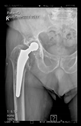

The radiological examination allowed us to verify the close bone-to-implant contact and the unchanged position of the implant during follow-up.

3. Results

In all the cases operated with the above-described targeting procedure, the stems of the cups remained between the cortical bone surfaces without perforation of the linea terminalis, as shown by postoperative radiographs. There were no complicated surgical situations. In 16 cases, the wound healings were uneventful, and the hips were able to bear weight again after postoperative rehabilitation.